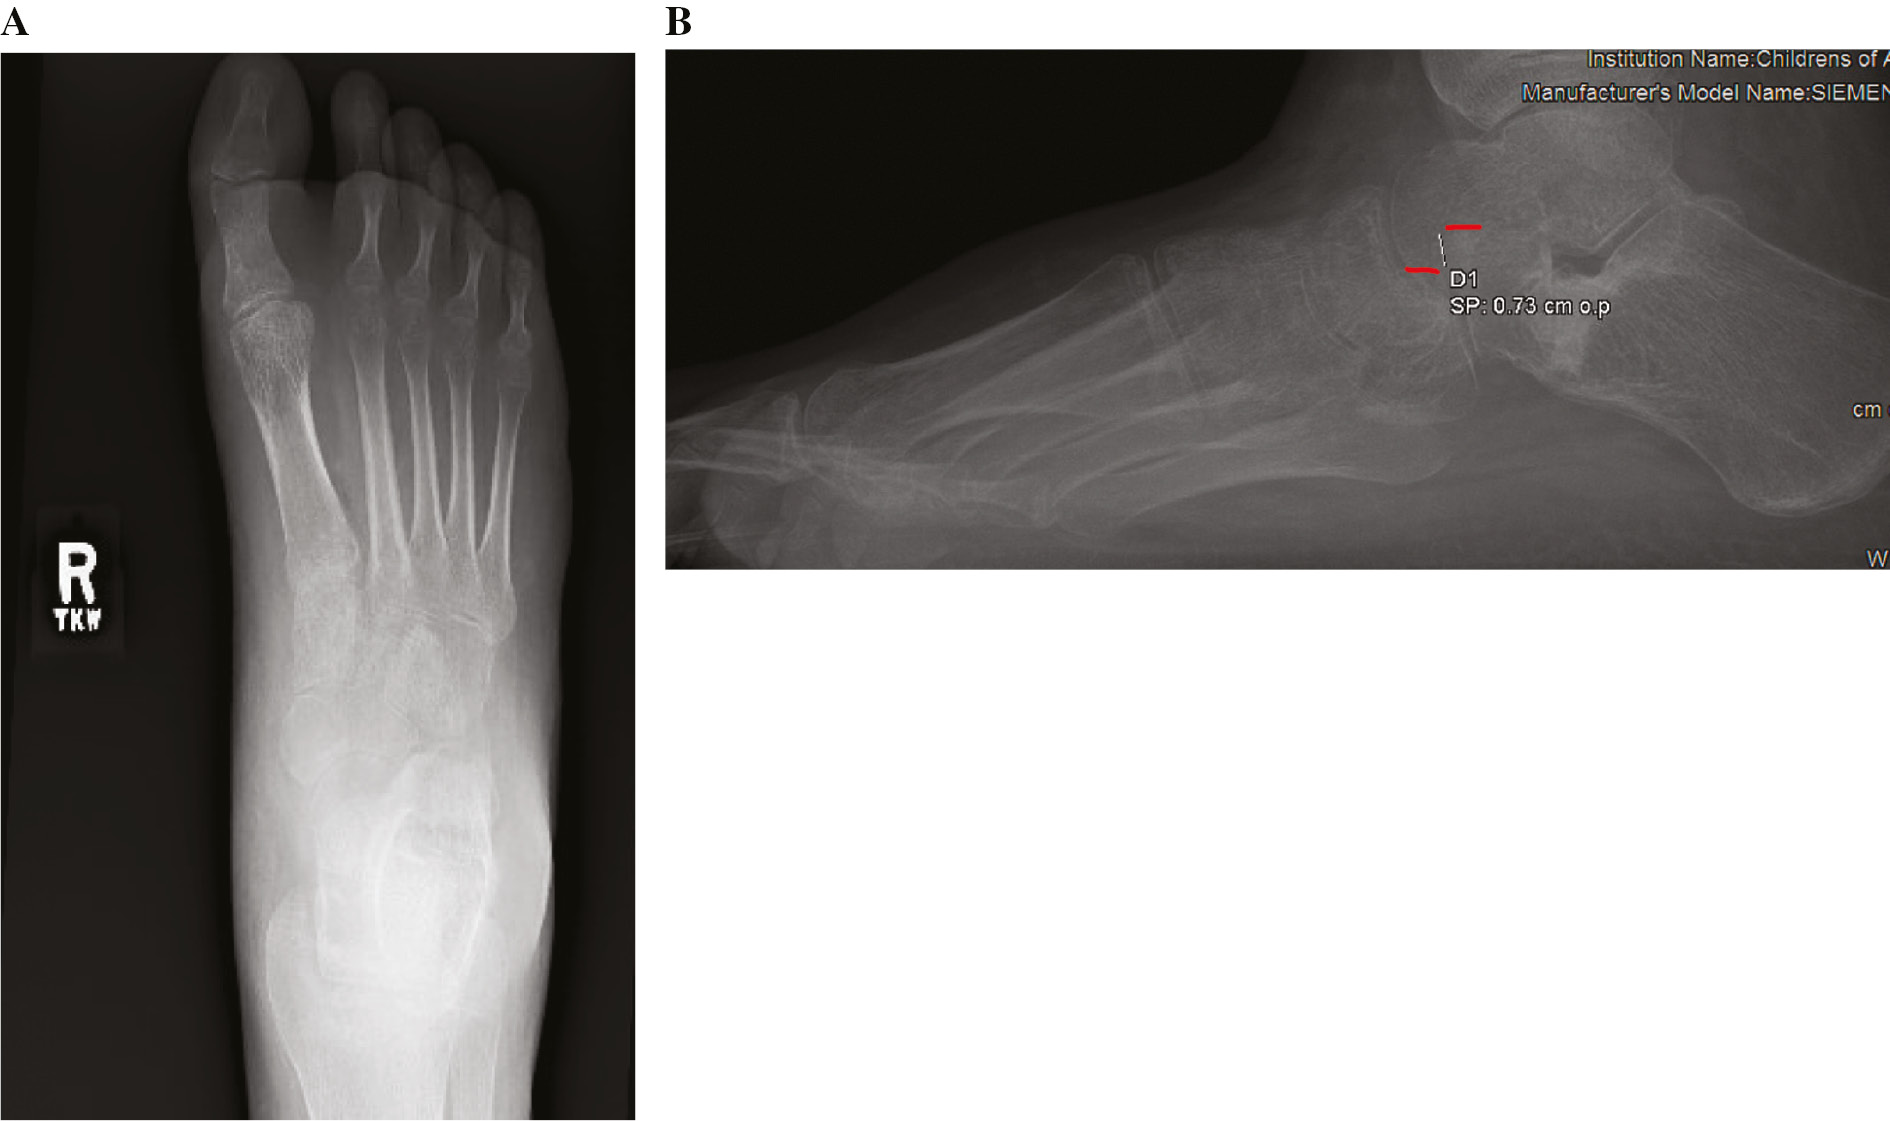

The patient is a 14-year-old male weighing 114.4 kg (>99th percentile) with a history of bilateral symptomatic pes planovalgus unresponsive to multiple modes of conservative treatment over 2 years. Physical examination demonstrates standing right hindfoot valgus and planus. The heel inverts with toe raise. In a subtalar neutral position, ankle dorsiflexion is 15 degrees short of neutral with the knee extended. Radiographs demonstrate planovalgus of the right foot (Figure 1).

Figure 1. (A) AP, (B) oblique, and (C) lateral preoperative radiographs demonstrating pes planovalgus and initial joint alignment of CC joint.

jposna2022567_fig1.jpg

Figure 3. (A) AP and (B) lateral 6-week postoperative radiographs demonstrating persistent CC joint subluxation.

jposna2022567_fig3.jpg

Figure 4. (A) AP and (B) lateral 12-week postoperative radiographs demonstrating persistent CC joint subluxation following pin removal.

jposna2022567_fig4.jpg